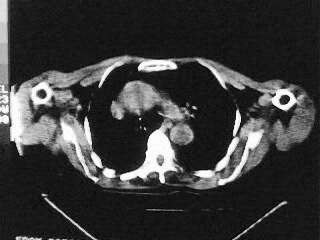

女,79,咳 嗽月余,无其它不适

后纵隔内左心房至肝左叶后方椎体中线偏左巨大软组织包块,其壁均匀比较薄,其内可见宽气液平。

考虑食管裂孔疝。建议钡餐检查